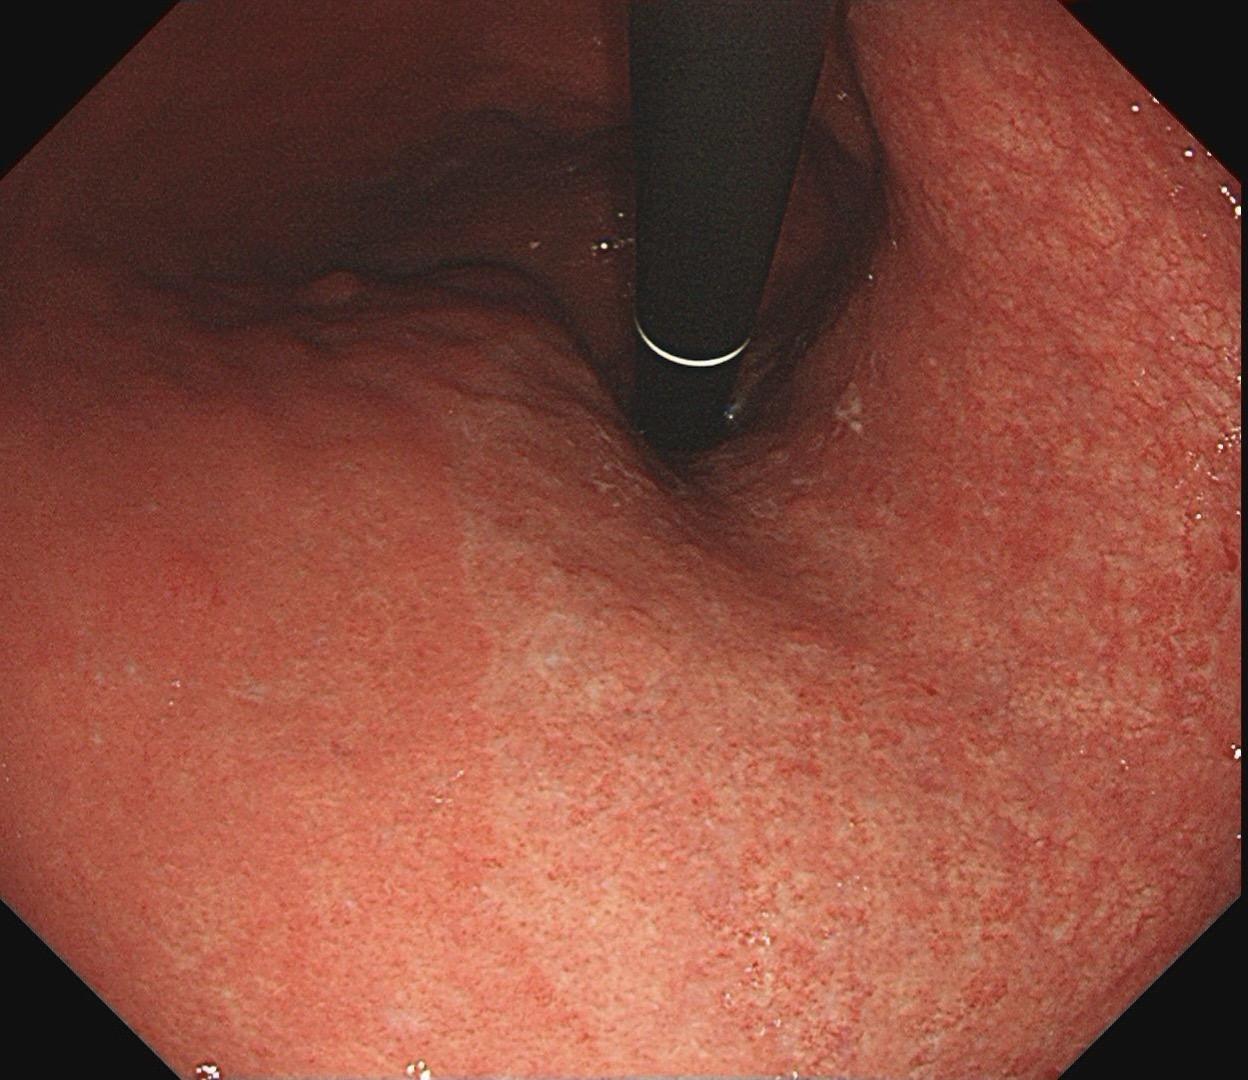

男,61岁,胃巨大褪色调病变。答案在最后一张图片,你猜对了吗? 患者因上腹部饱胀行胃镜检查,Hp阴性背景,胃窦至贲门下见一巨大褪色调病变,边界清晰,病变相对表浅,未见明显溃疡及隆起,胃壁较柔软,充气顺应性佳,予多点活检确诊,拟外科手术行全胃切除。做这么多年胃镜,还是第一次遇到这样的……